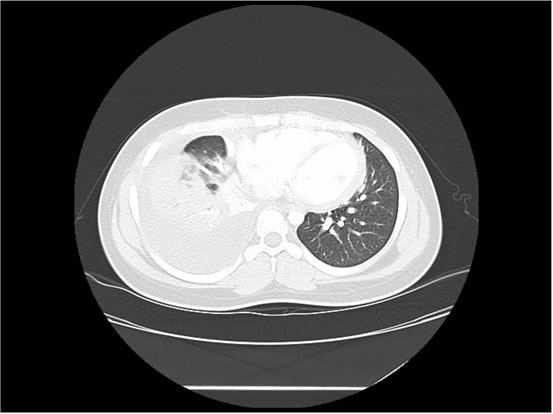

We ordered a CT scan with infusion of the chest

I will show you 12 CT-scan cuts.